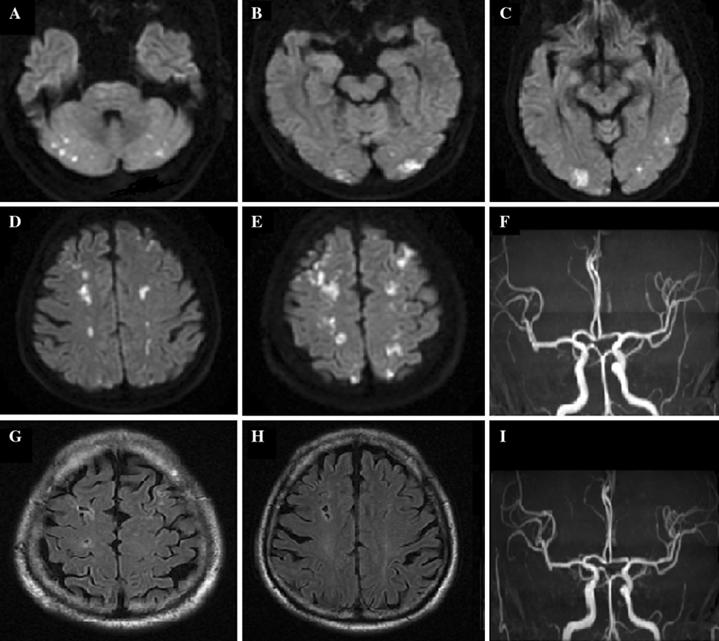

我院头颅核磁提示:大脑半球分水岭脑梗死